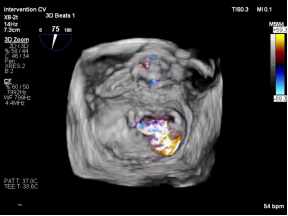

【图片2-5:术中TEE、夹持瞬间、术后效果图】

术后即刻评估显示,患者二尖瓣反流由重度(4+)降至轻度(1+),跨瓣压差维持在理想范围,肺静脉血流明显改善,手术取得良好效果。